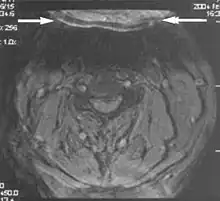

A motion artifact is one of the most common artifacts in MR imaging.[2] Motion can cause either ghost images or diffuse image noise in the phase-encoding direction. The reason for mainly affecting data sampling in the phase-encoding direction is the significant difference in the time of acquisition in the frequency- and phase-encoding directions.[1] Frequency-encoding sampling in all the rows of the matrix (128, 256 or 512) takes place during a single echo (milliseconds). Phase-encoded sampling takes several seconds, or even minutes, owing to the collection of all the k-space lines to enable Fourier analysis. Major physiological movements are of millisecond to seconds duration and thus too slow to affect frequency-encoded sampling, but they have a pronounced effect in the phase-encoding direction. Periodic movements such as cardiac movement and blood vessel or CSF pulsation cause ghost images, while non-periodic movement causes diffuse image noise (Fig. 1). Ghost image intensity increases with amplitude of movement and the signal intensity from the moving tissue. Several methods can be used to reduce motion artifacts, including patient immobilisation, cardiac and respiratory gating, signal suppression of the tissue causing the artifact, choosing the shorter dimension of the matrix as the phase-encoding direction, view-ordering or phase-reordering methods and swapping phase and frequency-encoding directions to move the artifact out of the field of interest.[1]